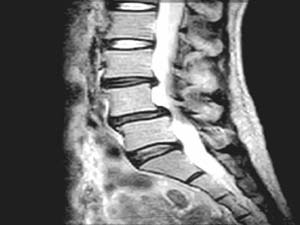

<Ãß°£ÆÇ

Å»ÃâÁõÀÇ MRI >